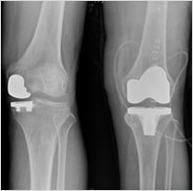

마취는 일반적으로 척추 마취를 시행하며, 수술시간은 1시간에서 1시간 30분 정도 걸리나, 이는 환자의 무릎 상태에 따라 다릅니다. 관절의 썩거나 파괴되어진 부분을 제거하고, 특수 금속으로 된 인공관절을 양쪽 뼈에 덧 씌우고, 그 사이에 관절 연골 역할을 하는 폴리에틸렌이라 불리는 특수한 플라스틱을 삽입하여 그 사이가 매끈하게 움직이게 하는 수술입니다. 수술후에 통증이 사라지고, 정상인과 같이 생활할 수 있기 때문에 최근 급속도로 증가추세에 있는 시술입니다.

저희 메트로 병원에서는 어께관절 , 팔꿈치 관절, 발목 관절등 여러 관절에서 인공관절 수술이 가능 하며, 특히 고관절(엉덩이 관절) 과 무릎 관절에 대해 많은 수술을 하고 있습니다.